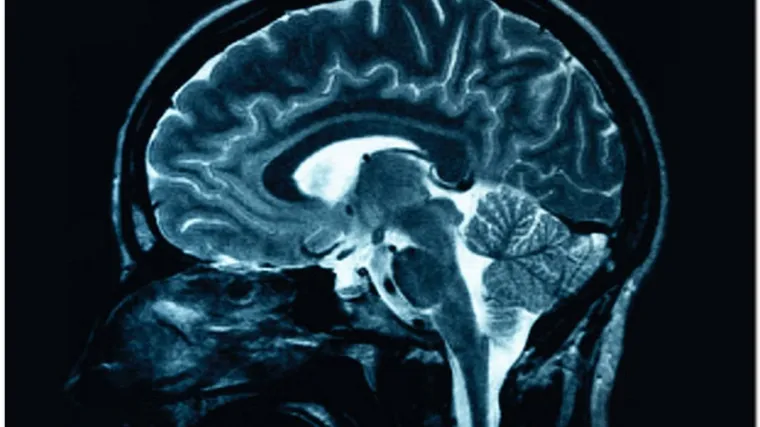

Liječnici uspjeli 'pročitati misli' pacijentu u komi!

Kanađanin Scott Routley već 12 godina vegetira. Iako su liječnici smatrali da on nije svjestan ničega oko sebe te da ni na koji način ne može komunicirati s okolinom, sada su uspjeli utvrditi suprotno.

Još 2010. godine neuroznanstvenici su utvrdili da je moguće komunicirati s pacijentima koji su u vegetativnom stanju koristeći fMRI uređaj, a sada su to uspjeli u praksi.

Naime, Kanađanin Scott Routley, koji je u komi 12 godina, uspio je liječnicima mislima reći da ne osjeća nikakvu bol.

Scott je doživio tešku prometnu nesreću i otada vegetira. Liječnici su smatrali da on nije svjestan ničega oko sebe te da ni na koji način ne može komunicirati s okolinom.

No profesor Adrian Owen uspio mu je pomoći fMRI uređaja "pročitati misli". "Scott nam je pokazao da je svjestan te da njegov mozak radi. Skenirali smo ga nekoliko puta i uzorak aktivnosti njegova mozga nam pokazuje da Scott odgovara na naša pitanja", rekao je Owen te dodao kako vjeruju da Scott zna tko je i gdje se nalazi.